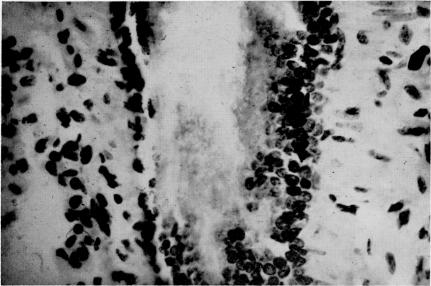

An experimental model for human mycoplasma disease.

Yale J Biol Med. 1968 Apr-Jun;40(5-6):436-43.